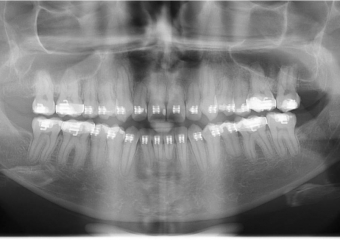

Raio x após a cirurgia